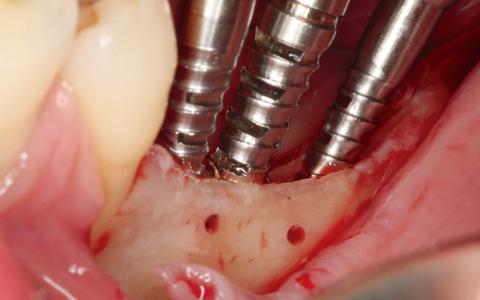

Paciente de 45 años a la que le extrajeron los dientes 45 ,46 y 47 hace unos 17 años. Paciente fumadora sin alteraciones sistemicas, con biotipo fino y una cresta mandibular de 2 mm a nivel transversal.

Plan de tratamiento: Técnica de expansión y colocación de implantes en dos tiempos. Expansión ósea y colocación de tornillos de osteosintesis como parte de la regeneración ósea.